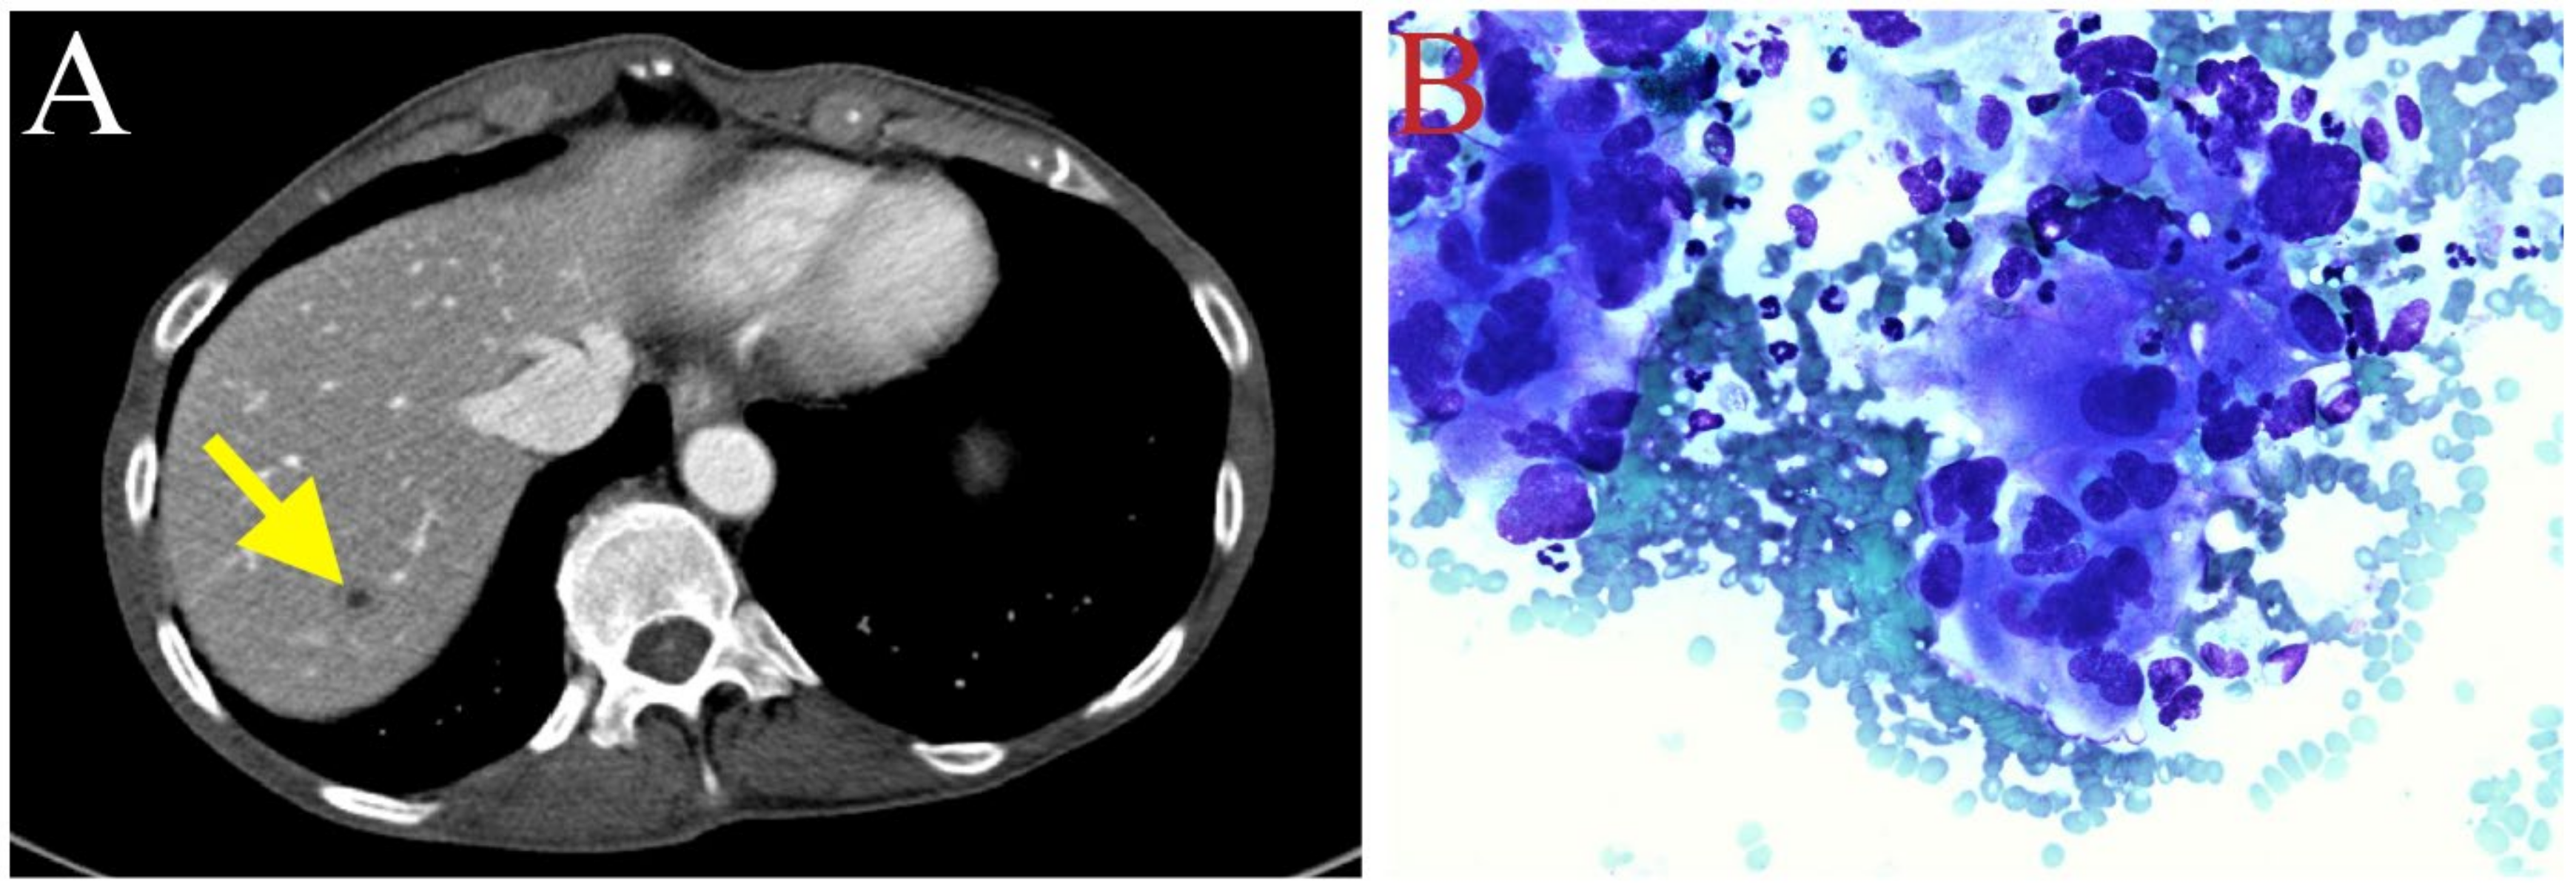

2. Case Description